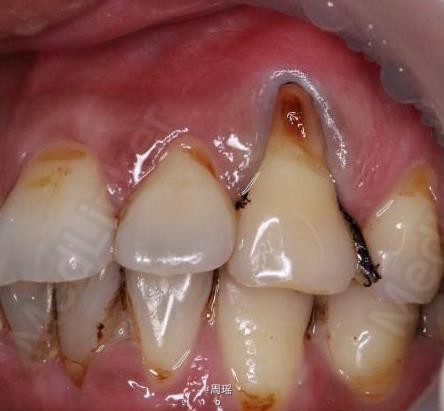

楔状缺损的充填

楔状缺损

患者,男,40岁,左上第一前磨牙楔状缺损来诊。平素体质一般,无系统性疾病和高血压、心脏病等病史,无药物、食物过敏史。

树脂修补

效果很好,患者满意。